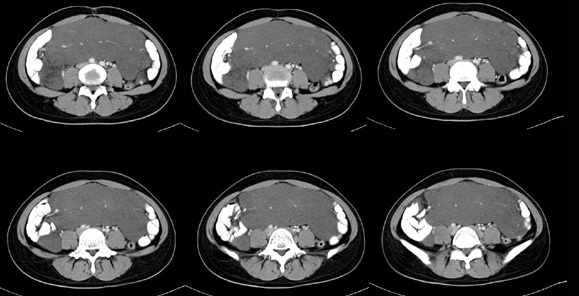

女性,28岁,停经3月,腹部膨隆1月,产前检查发现腹部占位

{肿块中心ct值27hu,增强后,动脉期、门脉期均无明显强化)

继续发